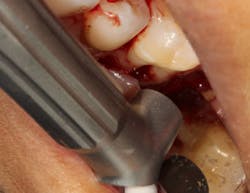

Another advancement in the field of periodontal regenerative medicine has been due to the use of growth factors, proteins, and stem cells. The ability to repair/regenerate a diseased tooth is often dependent upon the extent of the defect, namely the number of bone walls that are left surrounding the tooth. The more bone walls a tooth has left around it (maximum of four), the more blood supply, containment, and space maintenance your graft material will have (figure 5). Bone defects that have three to four walls missing are the hardest to repair and may be slated for extraction (figure 6). By adding growth-stimulating factors to your regular bone grafts (figure 7), an increase in osteopromotive potential occurs that can have the ability to overcome a deficiency of bone walls. (15) Simply stated, your bone graft can become alive, and teeth that were once unable to be repaired now have a chance.

Figure 7: Same tooth undergoing periodontal regeneration surgery with anorganic bovine bone (Bio-Oss Collagen, Geistlich Biomaterials) and platelet-derived growth factor (PDGF)